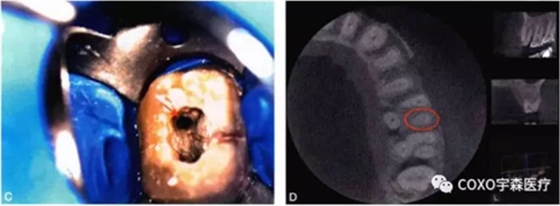

細小鈣化根管的根管口,即使是在口腔手術(shù)顯微鏡下,也不容易被發(fā)現(xiàn)。在鈣化根管的早期,鈣化牙本質(zhì)的顏色可能與周圍正常牙本質(zhì)不同,因此,多數(shù)情況下,利用口腔手術(shù)顯微鏡能夠發(fā)現(xiàn)根管所在位置。有的鈣化根管牙本質(zhì)與周圍牙本質(zhì)顏色相似,難以區(qū)分,此時借助手術(shù)顯微鏡的高倍放大作用,結(jié)合根管解剖知識,仔細觀察顏色的細微差異,有助于提高探查根管口的成功率。完全鈣化的根管,表現(xiàn)為均質(zhì)的硬組織結(jié)構(gòu),有時與正常牙本質(zhì)結(jié)構(gòu)難以區(qū)別,當(dāng)采用各種方法均無法疏通時,為了避免產(chǎn)生新的并發(fā)癥,不宜強行疏通,可定期追蹤觀察(圖4-2)